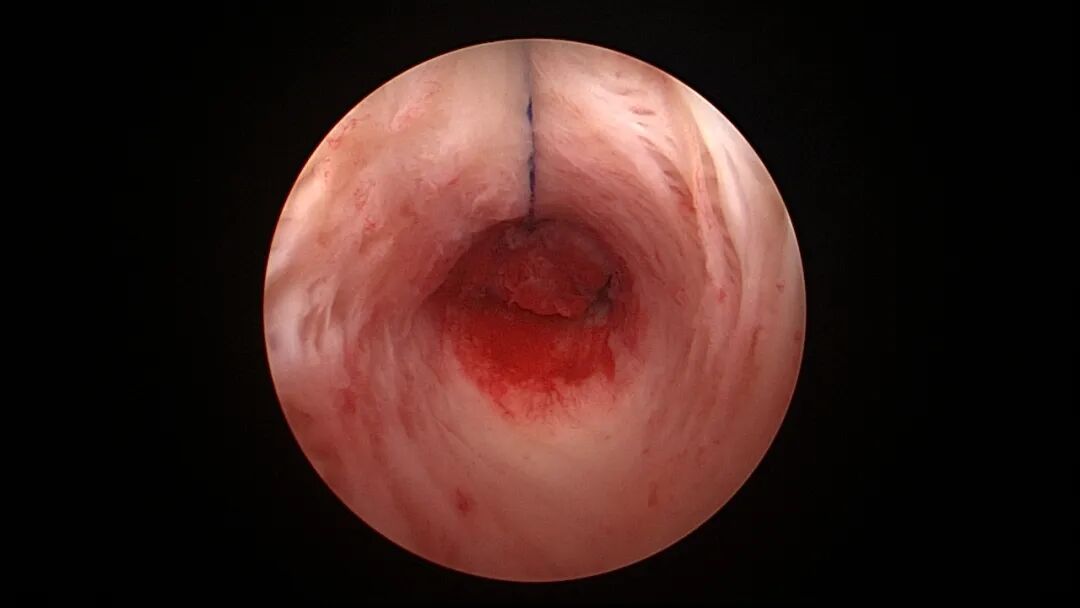

宫腔上段各壁都可以缝合固定,必须缝合到子宫肌层,缝合前最好去除较厚的内膜,显露基底层,避免仅缝合到内膜,节育环随月经脱落。使用冷刀系统操作镜,宫颈扩张到9号扩宫棒以上,宫颈管足够宽松,避免镜鞘与环纵臂紧贴卡压,摩擦阻力大会将环带出,撕裂缝合处组织,导致固定失败。冷刀系统抓钳夹持4-0不可吸收带针线进入宫腔(可以用中弯钳将带针线盲视下送入宫腔),将针尖扎进宫壁少许,再夹持针尾缝合,边进针边调整夹针位置,同时旋转持针钳柄及镜鞘,顺势完成弧形进针缝合。完成缝合后拉出带针线,线尾端缝线中段套扎固定节育环顶端,将环装回推杆送入宫腔,稍拉紧缝线,使节育环贴近宫壁缝合处。会阴部缝针端及线尾端两根线打韦斯顿结或田纳西结,还有路德结、Chula结、邓肯结、SMC结等多种滑结可供选择,将结推送至节育环附近,宫腔内靠近线结剪断缝线,宫颈外口剪断环尾丝(可在环送入宫腔前剪断)。

宫腔镜下节育环缝合固定注意事项:腺肌症子宫、终止妊娠后子宫,子宫长径大于7cm者,或盆腔粘连、膀胱充盈牵拉子宫者,宫深可能超过12cm,宫腔很大,尤其是肥胖病人,宫腔镜器械长度无法到达宫底,缝合很困难,可能无法看到宫腔后壁,甚至找不到附着在宫腔后壁的缝针,偶有放弃缝合固定病例,待药物治疗、子宫复旧及器械充分准备后择期再做固定。终止妊娠后子宫敏感,收缩放松频率快,在放松时间段无法完成缝合操作时,手术时间可能延长,因此清除胚胎后不要急着用缩宫素,否则影响缝合操作。取胚或内膜吸刮后宫腔有出血,视野不清,缝合比较困难,调高膨宫压会有改善。4-0线很细,很难在同一个部位打方结,打单结即可,肌层对单结的卡压足够固定节育环,甚至不需要肌层卡压固定结,仅仅一个限位结就足够固定节育环(体外打结很容易,多打几个结也无妨)。三种简化方案核心都是避免推结,费时费力,可能推结不到位,或过度牵拉撕裂组织,导致固定失败。可以根据病人具体情况及医生擅长选择一种简化方案固定,也可以几种简化方案联合使用。